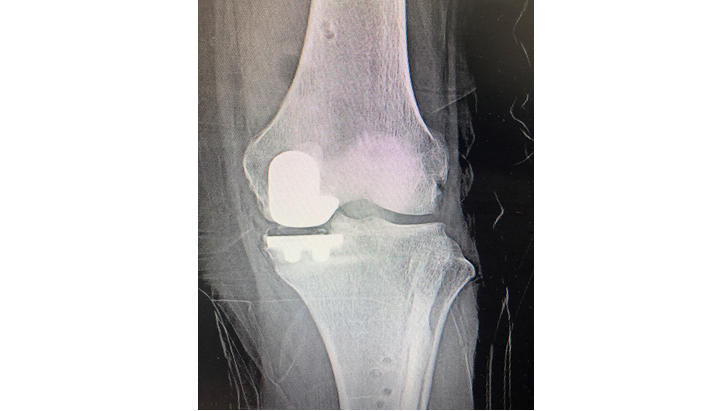

בשלב הראשון, מבוצע צילום CT של המפרק הפגוע. הצילום מוזן אל תכנת המחשב ובעזרתו מבצע האורתופד המנתח את התכנון הניתוחי. הלכה למעשה, התכנון המקדים מאפשר לאורתופד המנתח לקבל תמונה מלאה ומדויקת של מצבהמפרק ולתכנן את מהלך הניתוח עוד לפני ביצועו, לרבות סוג המשתל שיוכנס. כאמור, הניתוח מתבצע תחת הרדמה של חצי גוף בלבד. במהלך הניתוח, לאחר חשיפת המפרק, יוצבו קולטנים בשני צדדיו שמספקים תמונה תוך מפרקית מלאה. התכנה הממוחשבת תשווה בין מצב המפרק לבין התכנון הניתוחי ובעזרת הזרוע הרובוטית מבצע הרופא המנתח חיתוכים מדויקים של המפרק והחדרה של המפרק המלאכותי.

השימוש בטכנולוגיה הרובוטית מאפשר תכנון מקדים ומלא של מהלך הניתוח. בנוסף , השיטה המתקדמת מאפשרת פעולה כירורגית מצומצמת יותר והיא מקטינה את הסיכון לפגיעה ברקמות המצויות סביב המפרק. הדיוק האנטומי בחיתוכים המבוצעים על ידי הרובוט מצמצם את סיכוי לפגיעה רקמתית . בכל הנוגע להחדרה מדויקת של המשתל, הזרוע הרובוטית משפרת את סיכויי ההצלחה, ללא כל תלות במצב המפרק או באנטומיה האזורית. כל אלה מאפשרים שיקום מהיר יותר עם חזרה מהירה לפעילות, משפרים את שביעות הרצון מהפעולה הכירורגית ואת בטיחות הניתוח.כיצד מתבצע הליך השיקום לאחר הניתוחים הרובוטיים?